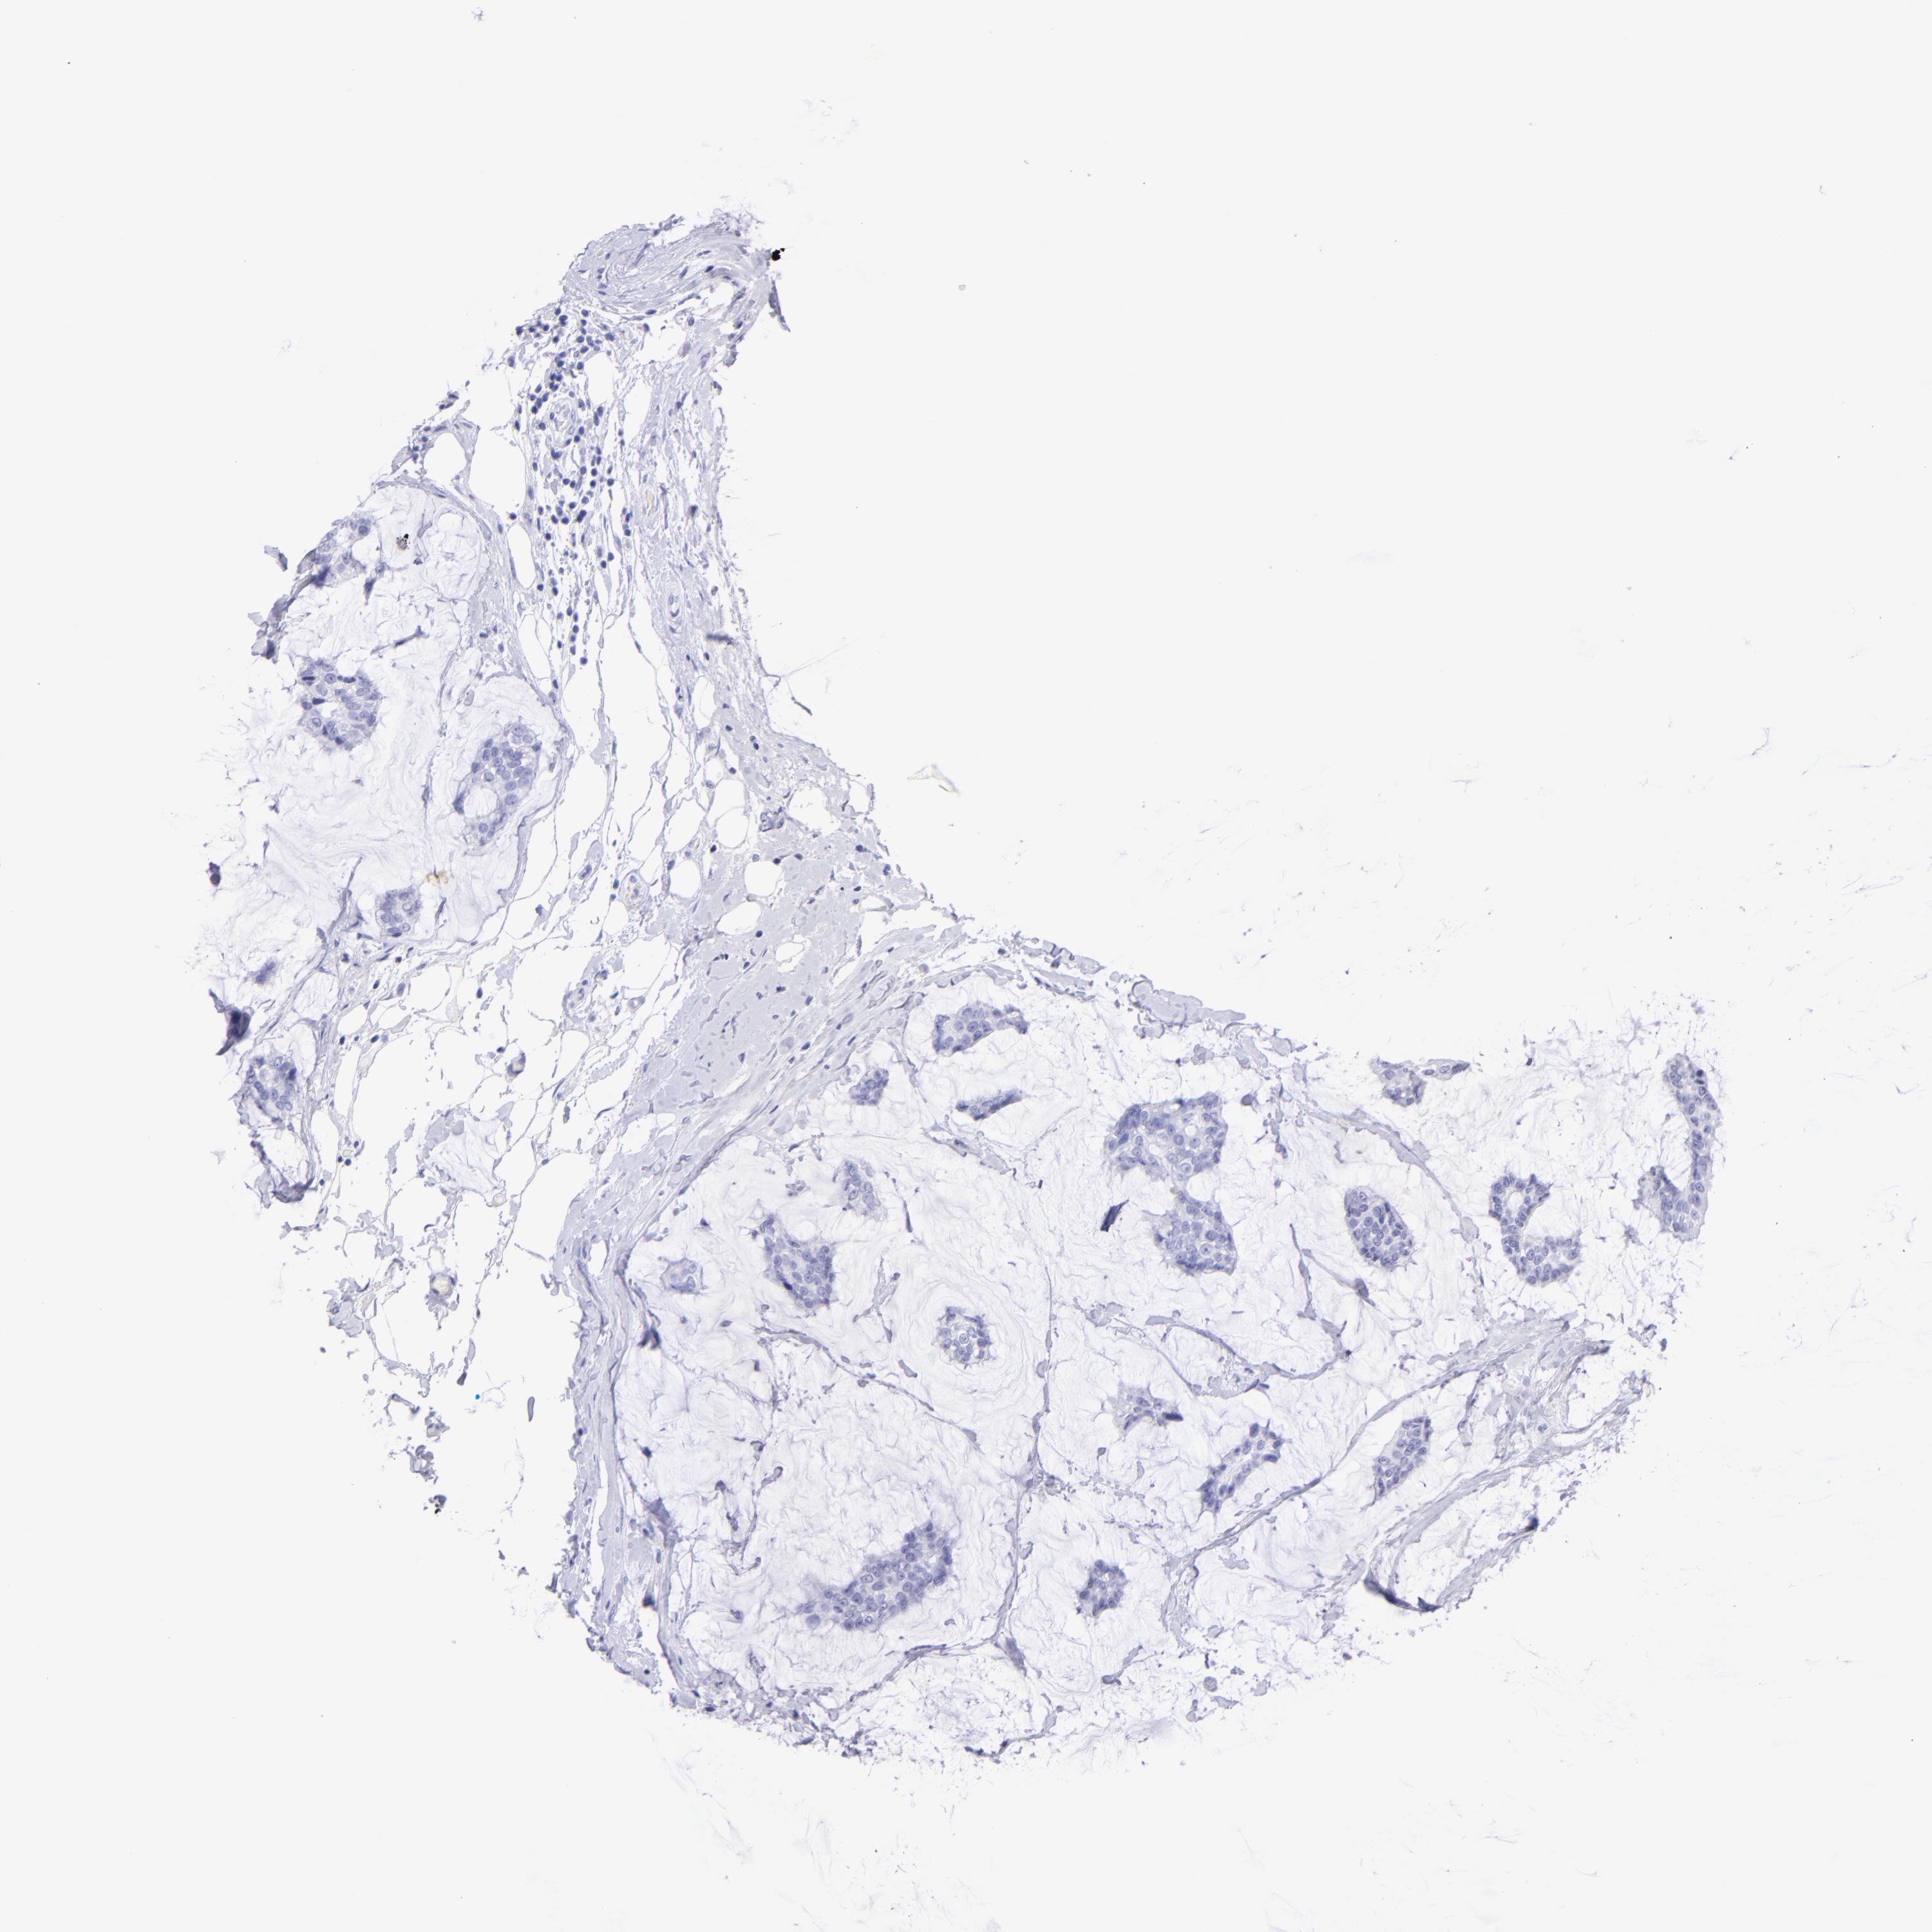

CANCER BREAST CANCER Show tissue menu

Breast cancer

Human cancer